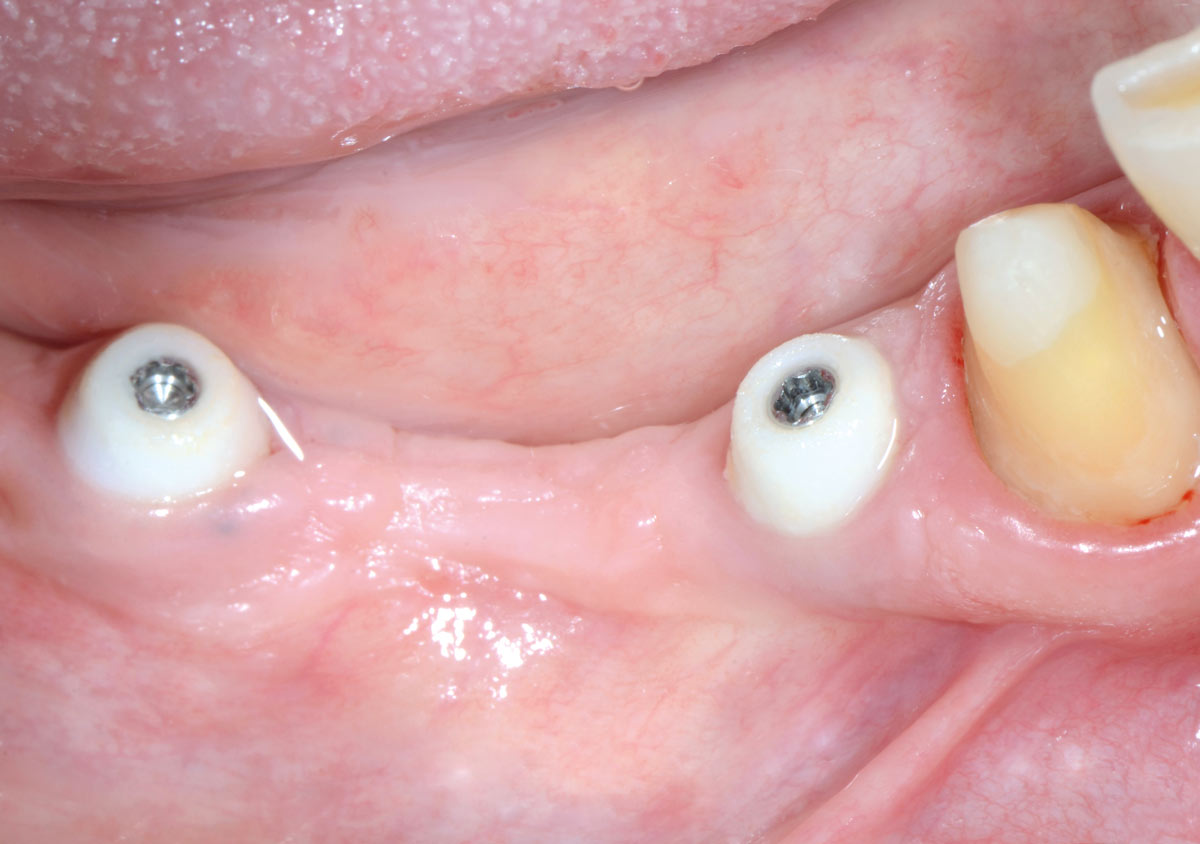

Multiple socket preservation in the mandibular with collacone® max – Dr. D. Jelušić